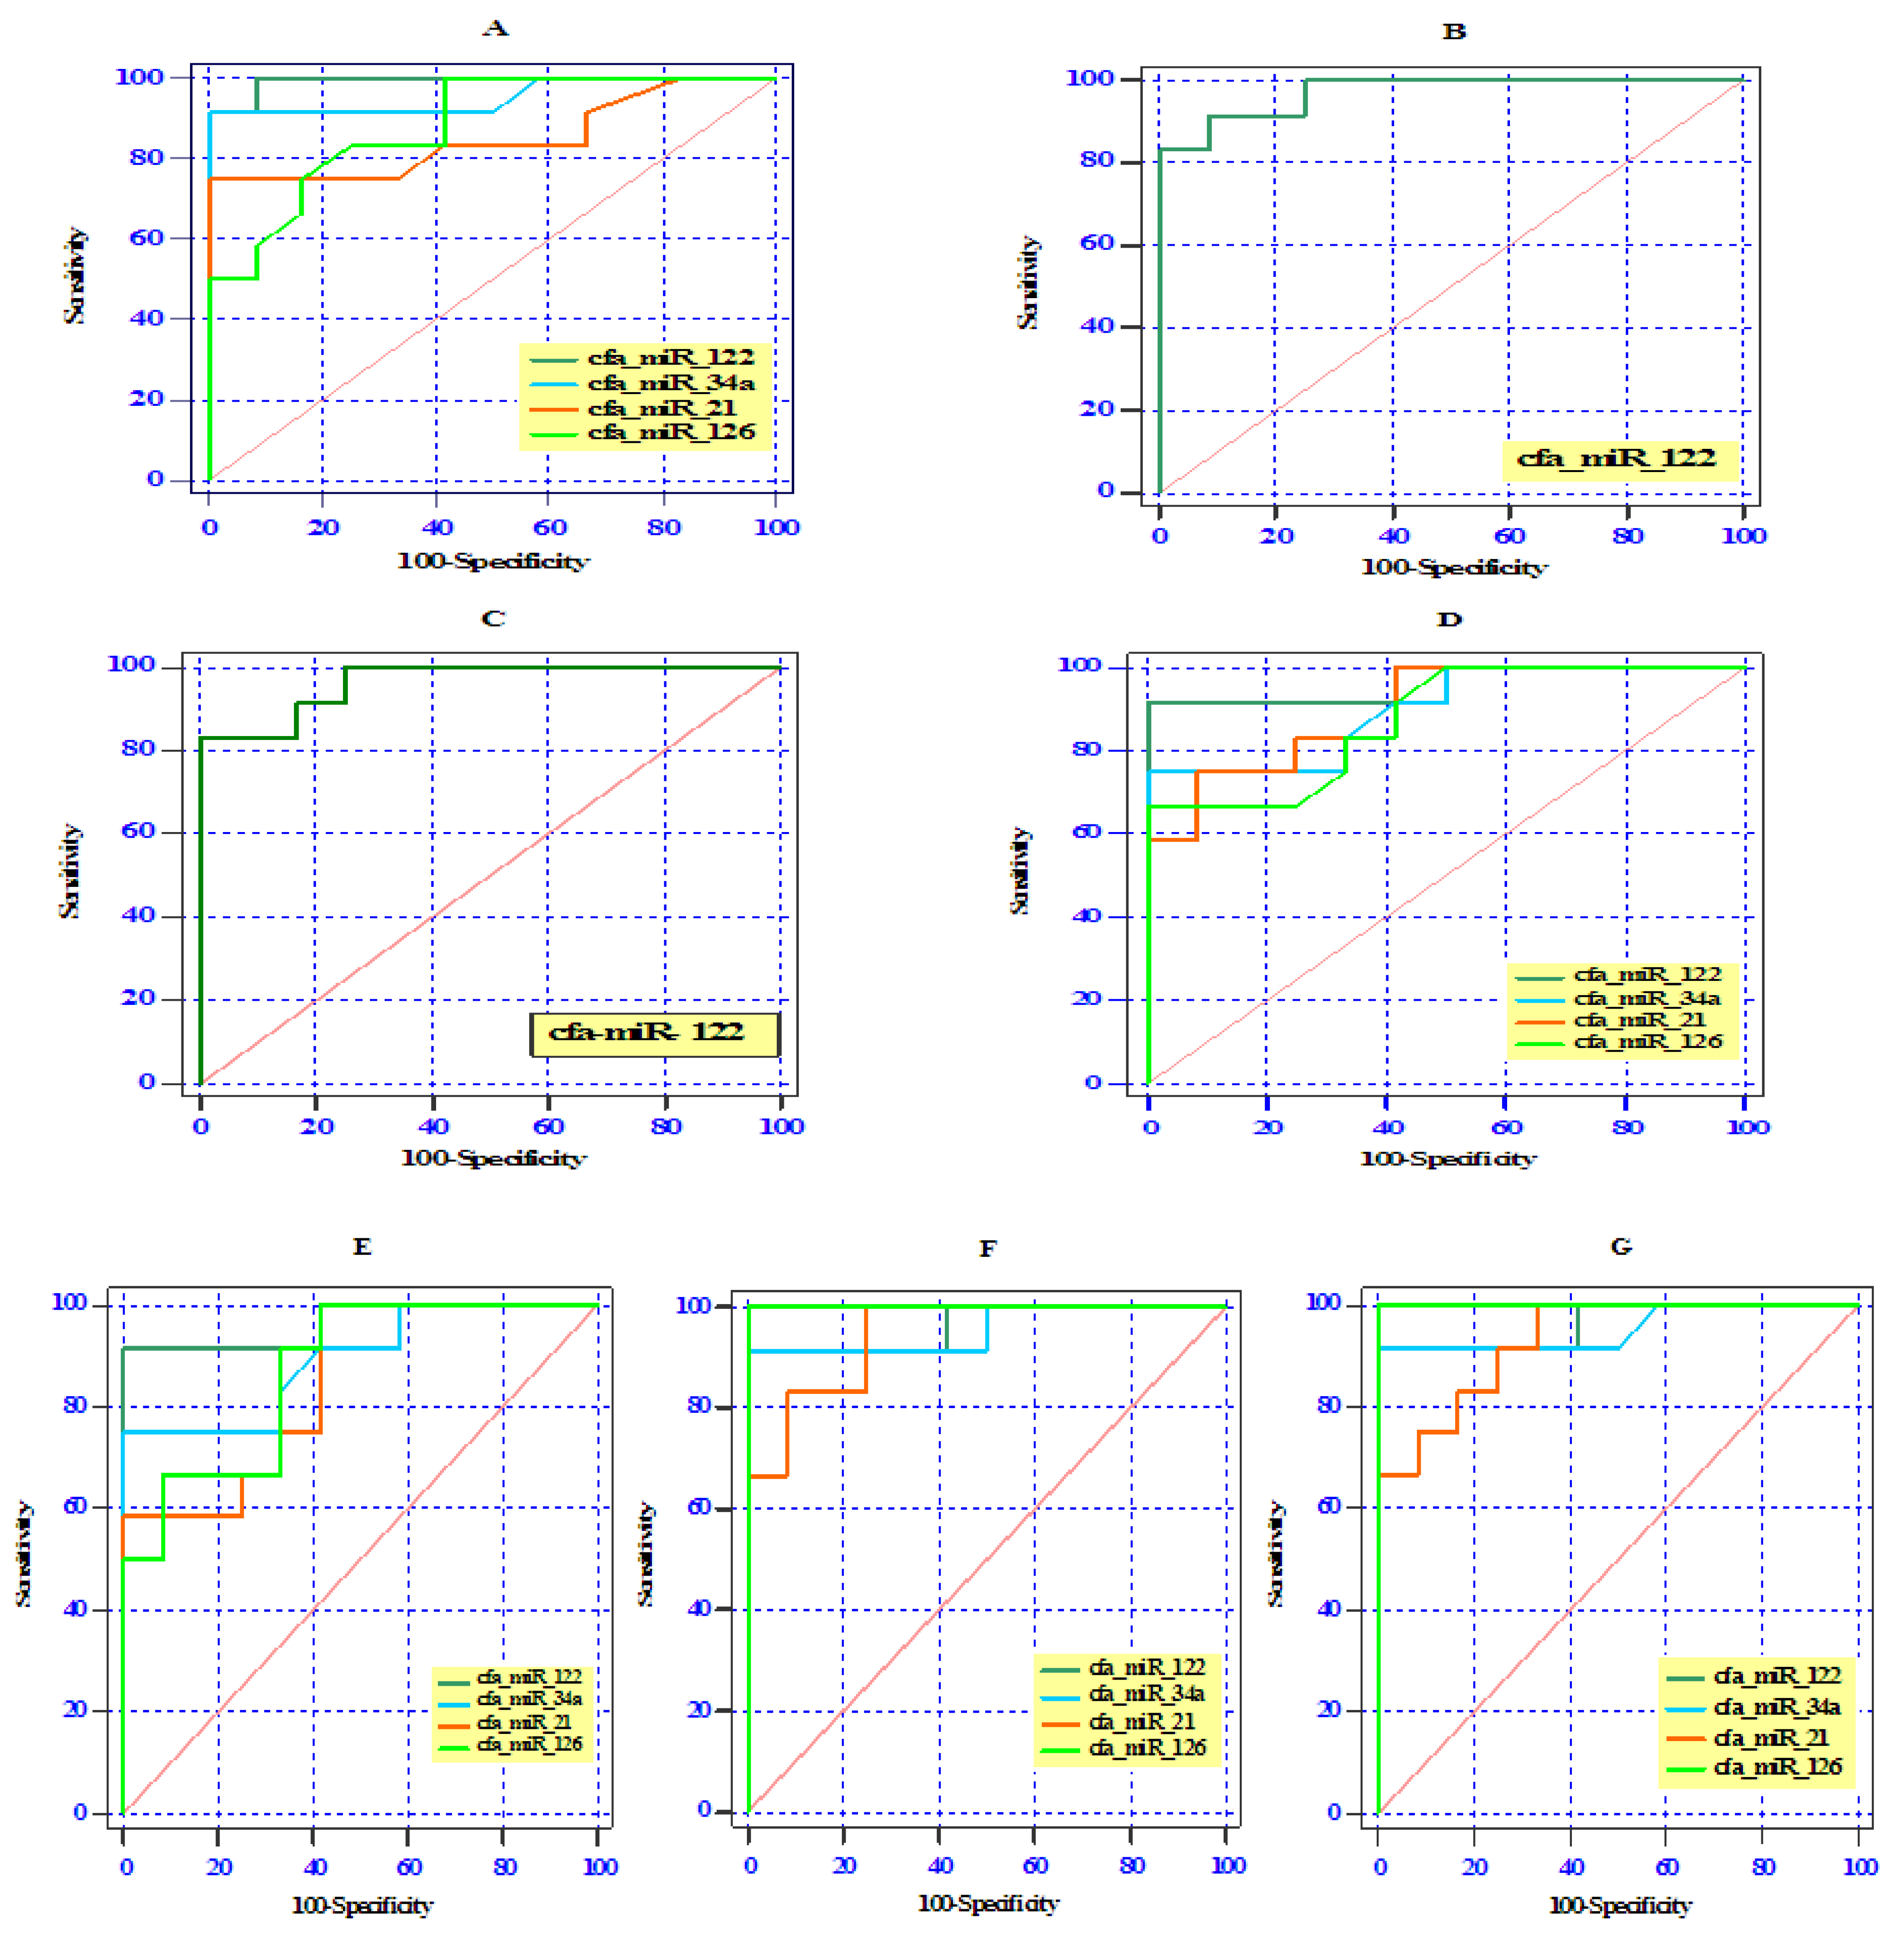

3.5. ROC Curve Analysis of Differentially Expressed Serum miRNAs